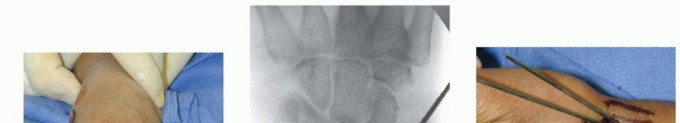

TECH FIG 2 • A. An incision is made over the radial styloid, and a K-wire is manually inserted into the fracture site. B. The wire is levered distally to correct the radial inclination. C. The wire is advanced proximally, using power, into cortical bone. D. An incision is made over Lister tubercle, and a wire is inserted into the fracture site. E,F. The wire is levered distally to correct the dorsal angulation and advanced proximally using power into cortical bone.

TECH FIG 3 • A,B. PA and lateral views demonstrating reduction of distal radius fracture. C. The incision is made over the radial styloid.(continued)

TECH FIG 3 •(continued)D. A pin is inserted retrograde into the radial styloid. E. PA radiograph demonstrating the course of the radial styloid wire. F. Two radial styloid wires and two dorsoulnar wires are in place. G. PA view showing fixation and the path of the wires. H. Lateral view showing fixation and path of wires. I. Pins are bent, cut, and covered above the skin. The pins are cut just beneath the skin, which is closed with a 5-0 nylon suture. Alternatively, the pins are bent and cut and left outside the skin ( TECH FIG 3I). A dressing and splint are then applied.3. Bridging External Fixator Application